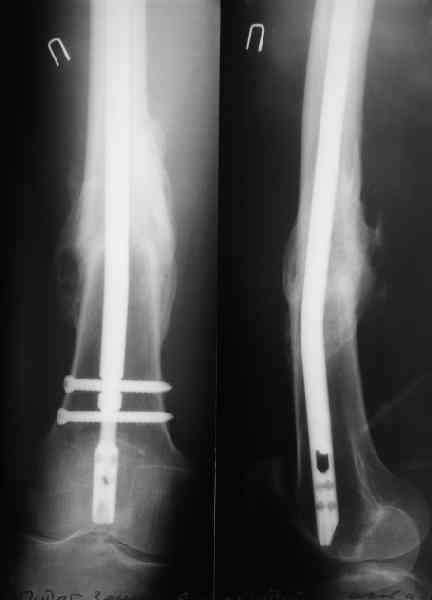

В приложении как раз видна эволюция использововшихся у нас большеберцовых гвоздей. Первый - дизайн как у UTN, второй - разнесены 45 градусные отверстия (зачем их вообще изначально так нелепо на одном уровне сделалм???), третий - убрано сиавшее лишним статическое отверстие, Herzog's bend перемещен более проксимально.

Насколько я помню, мы использовали этот вариант после знакомства с гвоздями SIGN, которые вообще одинаковые для бедра и голени, и дизайн у них большеберцовый.